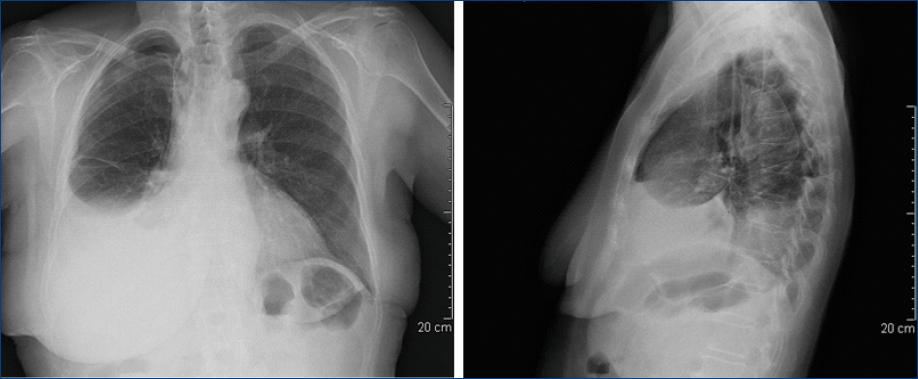

Paziente donna di 82 anni, non fumatrice, ex contadina, marito carabiniere deceduto nel 1996 per mesotelioma pleurico epitelioide senza chiara esposizione lavorativa all’amianto; all’anamnesi patologica remota distacco bilaterale della retina a 41 anni con successiva cecità; nel 1995 operata per neoplasia mammella sn. Dalla fine di agosto del 2014 comparsa di dispnea ingravescente e riscontro di versamento pleurico dx (Figura 1) per il quale il collega oncologo chiede il ricovero urgente in Pneumologia per la tipizzazione diagnostica e l’evacuazione terapeutica. L’EGA evidenzia ipossiemia (PaO2 60 mmHg); il BNP serico, l’ECG e i markers neoplastici sierici (CA 19-9, CEA, Ca 15-3, NSE) sono nella norma.

Figura 1.Rx torace: versamento pleurico dx senza spostamento del mediastino